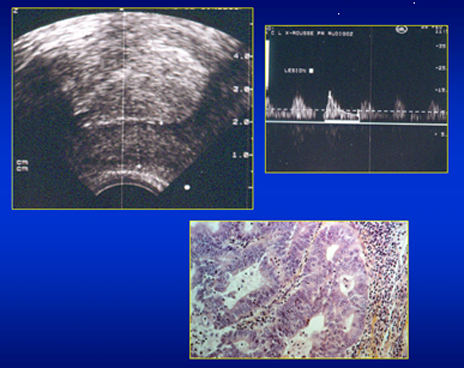

Endomètre épais et vascularisé; ana-path: Adénocarcinome endométrial